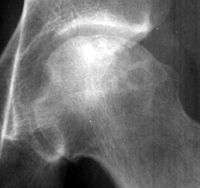

A radiograph of a left hip joint, which reveals a thin, curvilinear lucent line parallel to the cortical margin of the femoral head in a patient with avascular necrosis.

In radiology, the crescent sign is a finding on conventional radiographs that is associated with avascular necrosis.[1][2][3] It usually occurs later in the disease, in stage III of the four-stage Ficat classification system.[1] It appears as a curved subchondral radiolucent line that is often found on the proximal femoral or humeral head.[1] Usually, this sign indicates a high likelihood of collapse of the affected bone.[1] The crescent sign may be best seen in an abducted (frog-legged) position.[1][4]